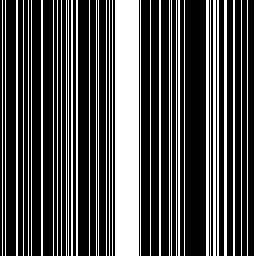

In experiments we include three common used types of undersampling masks such as the Cartesian pattern in (?), Radial pattern in (?) and Gaussian mask in (?). Fig.11 gives a visualization of the three kinds of patterns at a unified sampling ratio of 30%.

| Cartesian | Radial | Gaussian |